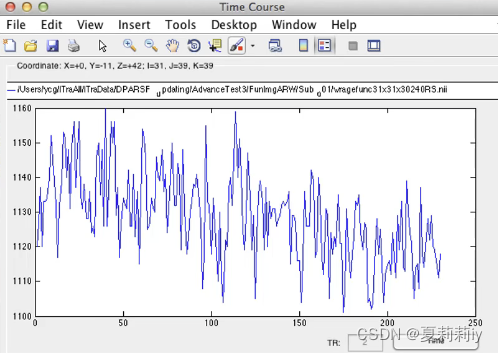

(4)Time Course:显示时间序列